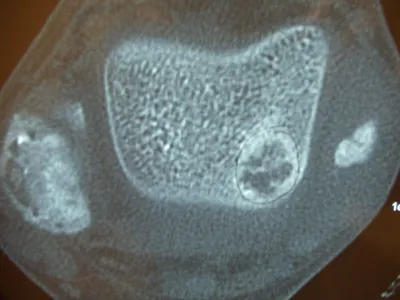

CT and MRI OCD Talus

The osteochondral fracture can be seen and it is loose. We are measuring the size on the last 2 pics.